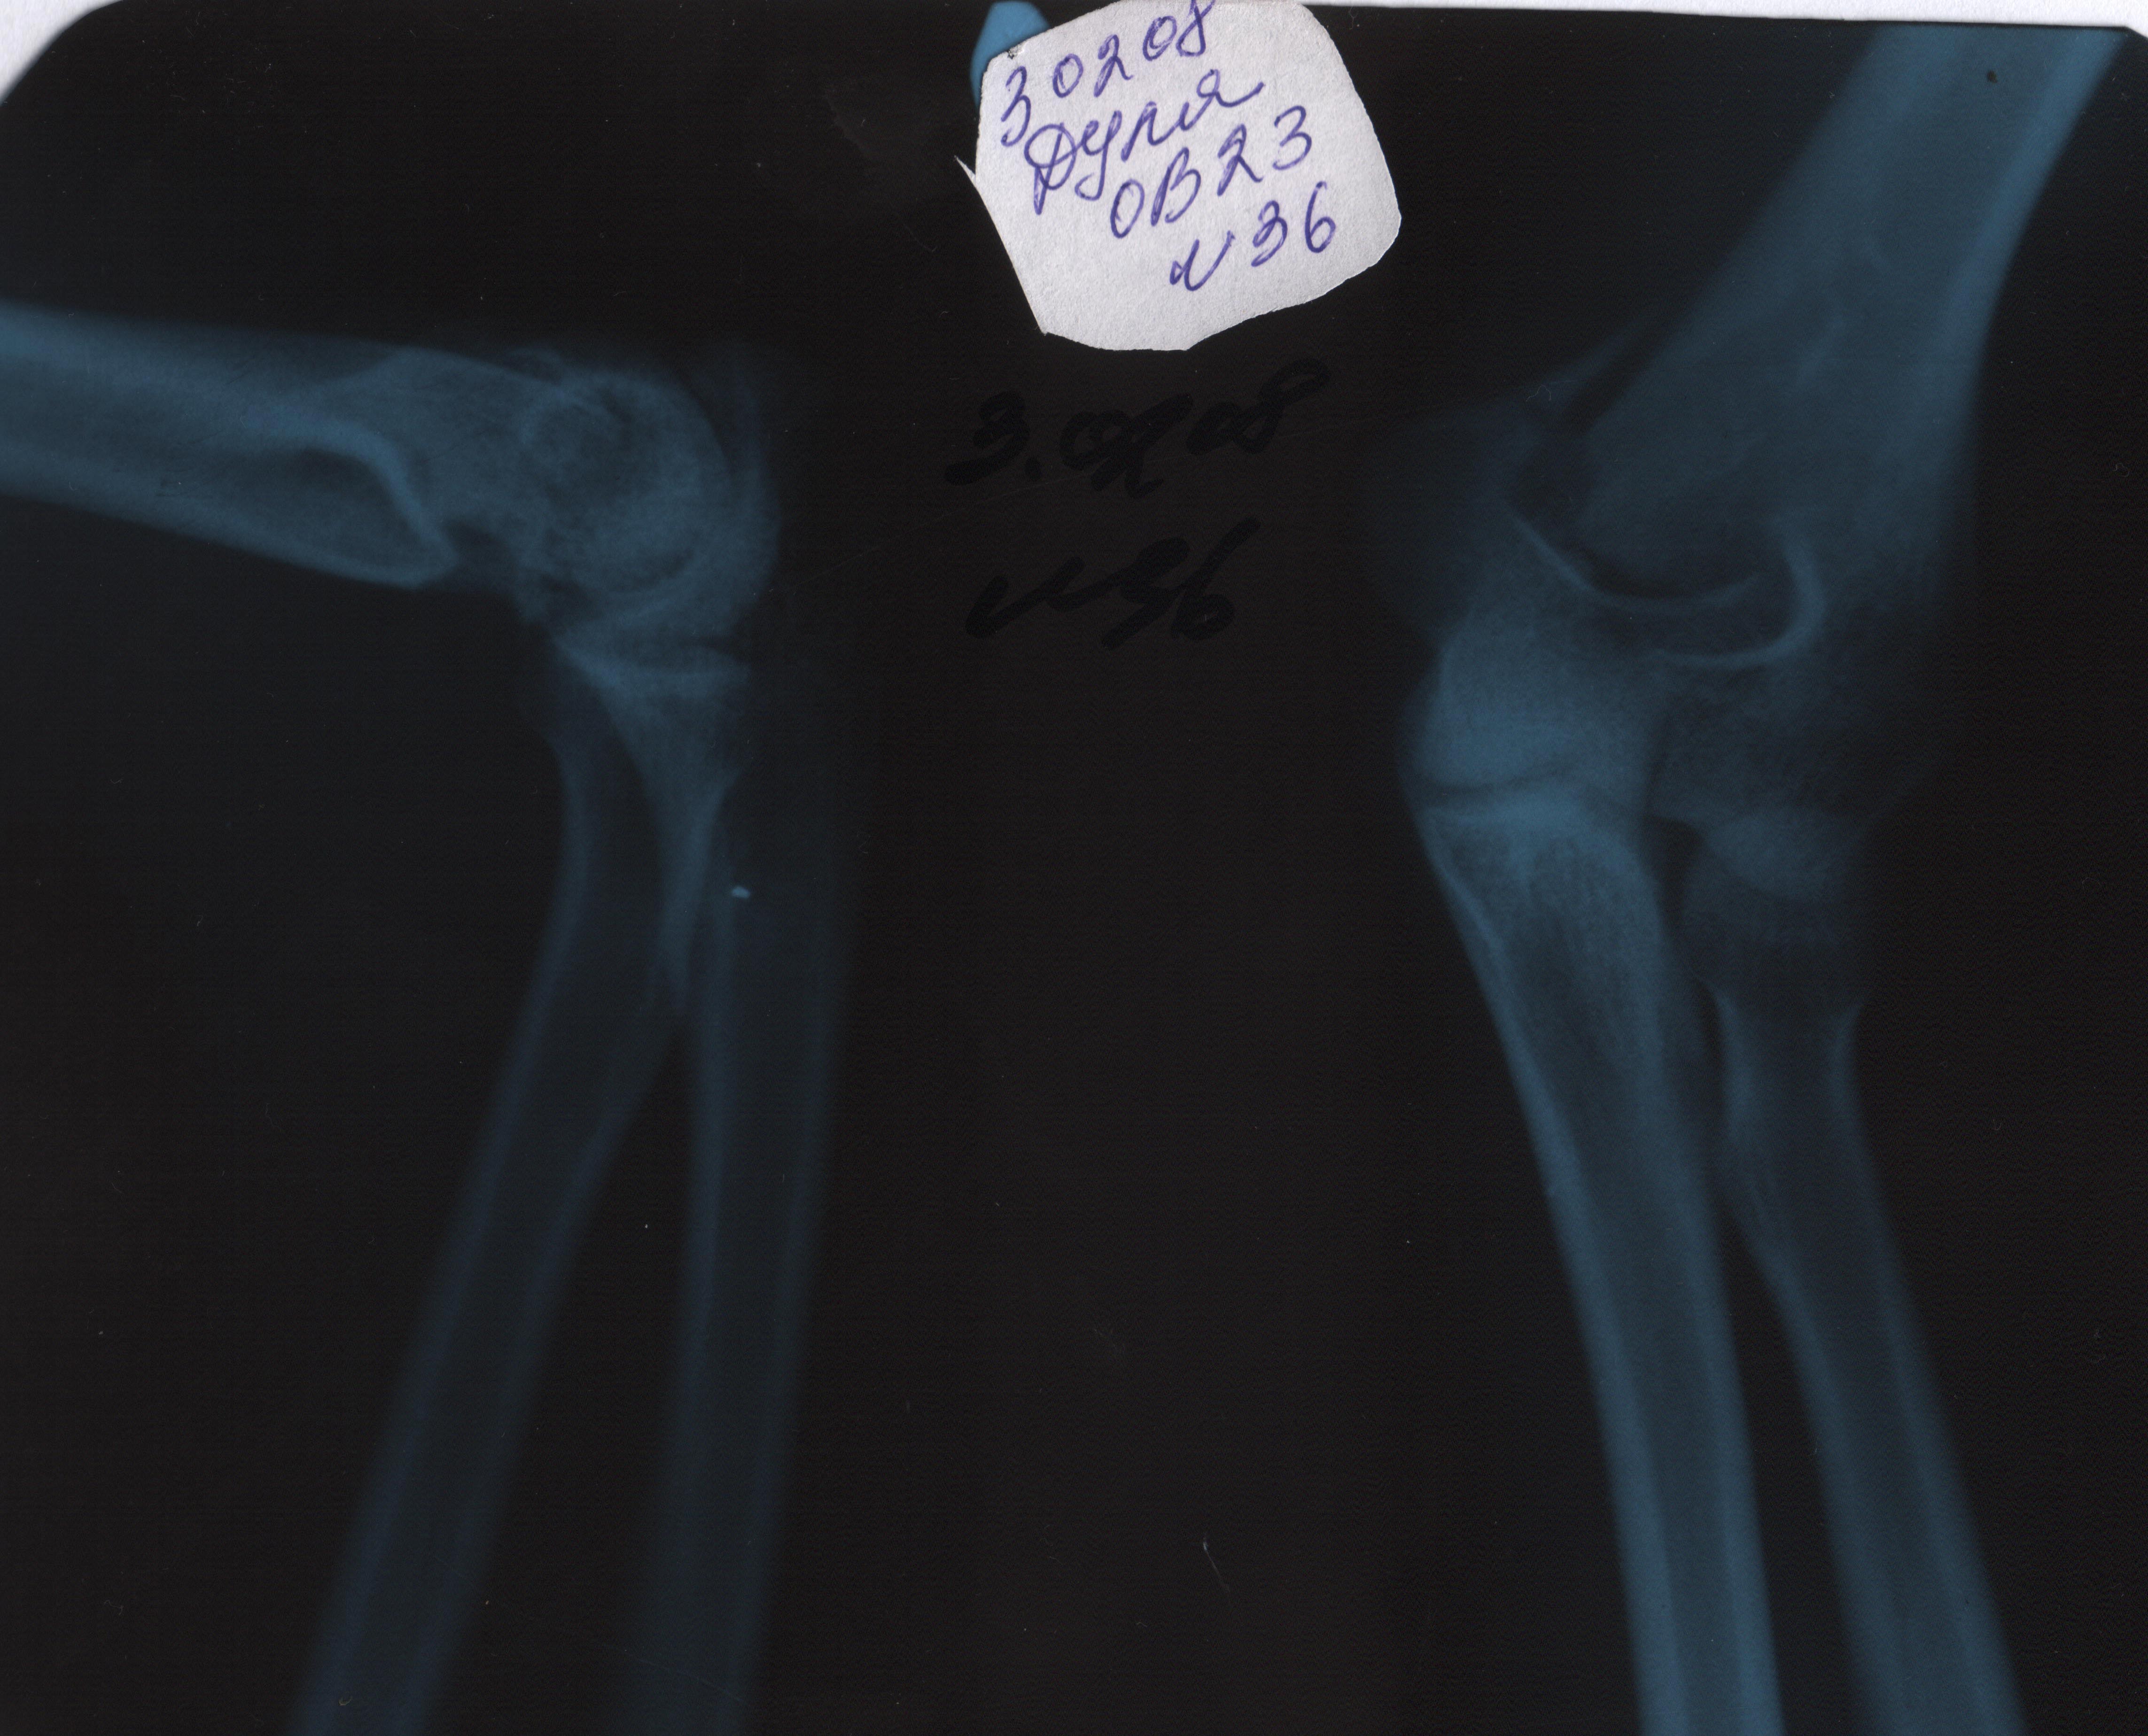

Полтора года назад я сломала руку.Диагноз - перелом дистального эпиметафиза левой плечевой кости (см аттач).Операции не было.6 недель гипса.В вашем институте прошла 2 месяца разработки.За что огромнейшее искреннее спасибо!Рука разгибается почти полностью,сгибая её, достаю до лица.Только при сгибании не могу поворачивать кисть.Совсем недавно при быстром сгибании стала появляться резкая боль.Сильная.Аж до потемнения в глазах и резкого рефлекторного разгибания (это тоже плохо-предметы из рук выпадают,случайно что-нибудь сметаю).Боль с внутренней стороны локтя.Жгущая.Уважаемые врачи! Очень прошу вас ответить.Можно ли от этого избавиться, и как?Будет ли это прогрессировать?